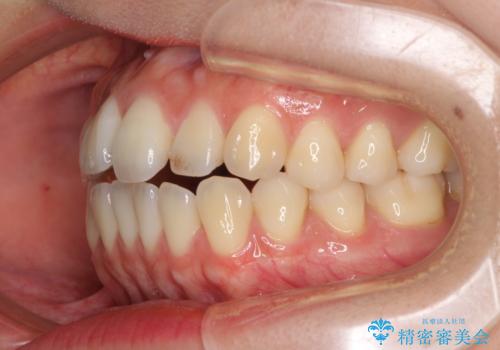

オープンバイトでかみにくい インビザラインによる矯正治療

- 前歯の上下スペースによる食べにくさを気にして来院された患者様です。

インビザラインにより上下の前歯の隙間を閉じていくこととしました。

上下の奥歯を圧下させるようにすることで、前歯を接触させるように計画しました。

上下の隙間に舌が入り込むことがオープンバイトの原因であったため、舌の筋肉のトレーニングも並行して行い、後戻りの抑制を図りました。